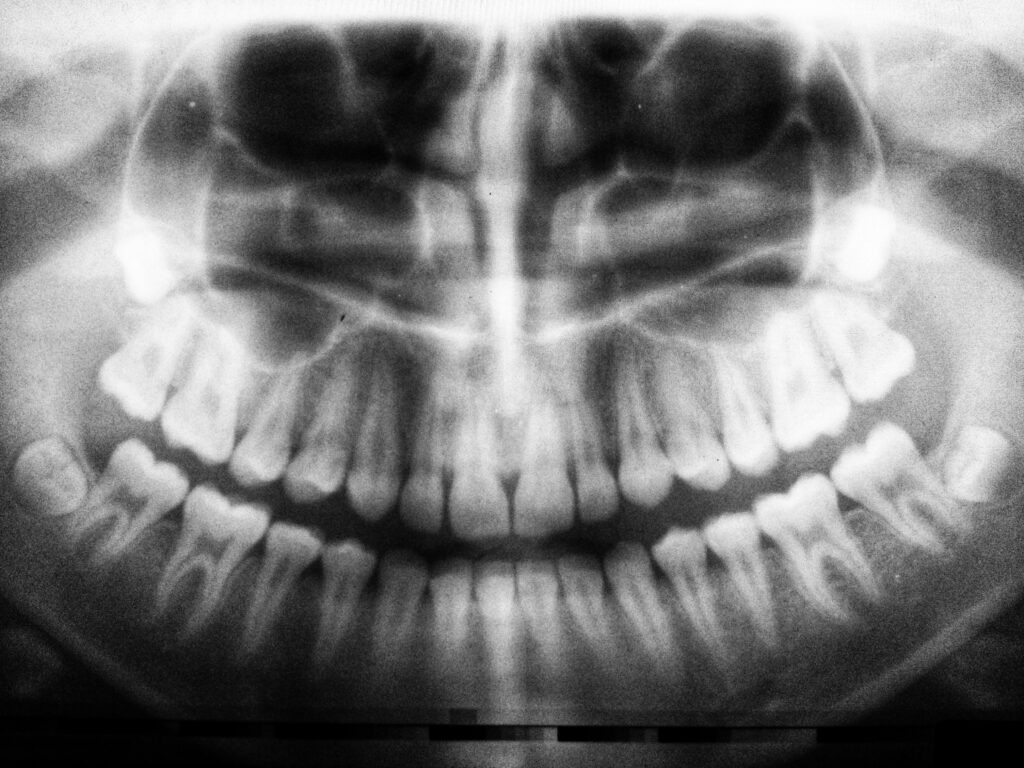

Зубы мудрости часто ассоциируются с юностью и взрослением, но на практике они могут стать причиной множества проблем. Хотя эти зубы могут быть полноценными частью зубного ряда, иногда их удаление становится необходимым шагом для поддержания здоровья полости рта. Это могут быть, например, анатомические ограничения. Многие люди сталкиваются с недостатком места в челюсти для третьих моляров. Когда зубы мудрости начинают расти, они могут занимать неправильное положение и давить на соседние зубы, вызывая дискомфорт, смещение и проблемы с прикусом. Удаление зубов мудрости в таких случаях помогает предотвратить износ остальных зубов и снижение их функциональности. Еще одна причина: возможность — увеличенный риск заболеваний. Поскольку зубы мудрости расположены в дальней части челюсти, они труднодоступны для очистки. Это делает их более восприимчивыми к кариесу и воспалению десен. Невозможность поддерживать эти зубы в чистоте может привести к инфекциям, которые могут распространиться на соседн

Также вокруг корней зубов мудрости могут образовываться кисты, которые часто остаются незамеченными, пока не начнут вызывать боли и другие осложнения. Эти кисты могут разрушать костную ткань, что требует более серьезного вмешательства. Удаление зубов мудрости на ранних стадиях помогает избежать хирургических операций и других сложностей в будущем.